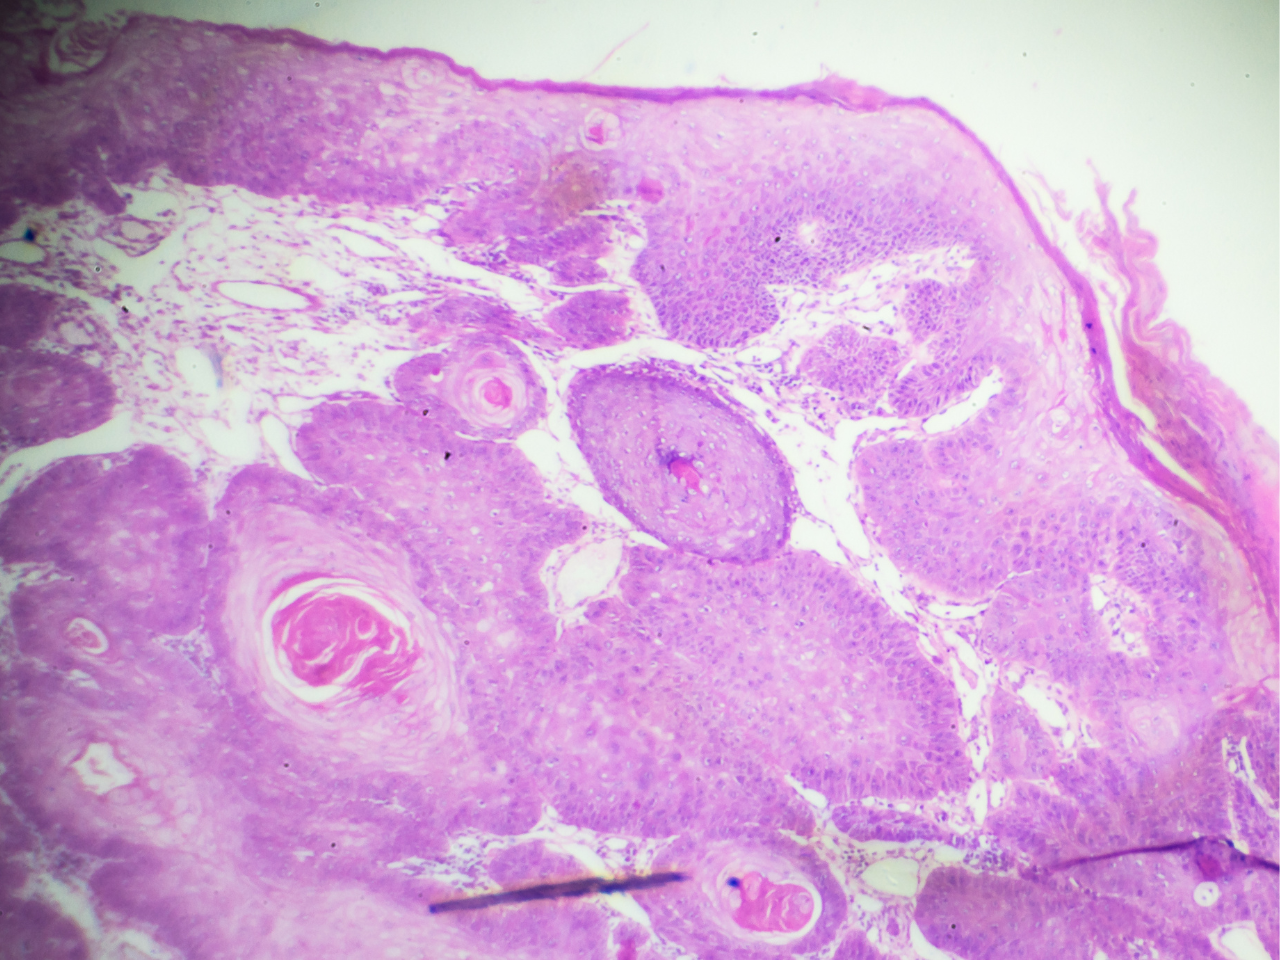

O carcinoma espinocelular cutâneo (CEC) origina-se do crescimento descontrolado de queratinócitos anormais, principalmente em locais anatômicos expostos ao sol. Se não tratados, os CECs podem penetrar nos tecidos subjacentes e metastizar.1

O relatório final da patologia deve incluir o subtipo histológico do tumor, incluindo o diâmetro (clínico, macroscópico ou microscópico), o grau histológico (grau de diferenciação celular) e a profundidade de invasão com a distância da camada granular da epiderme normal adjacente à base da amostra (em mm), o nível anatômico de invasão, além do tecido adiposo subcutâneo e a invasão perineural, se houver.6